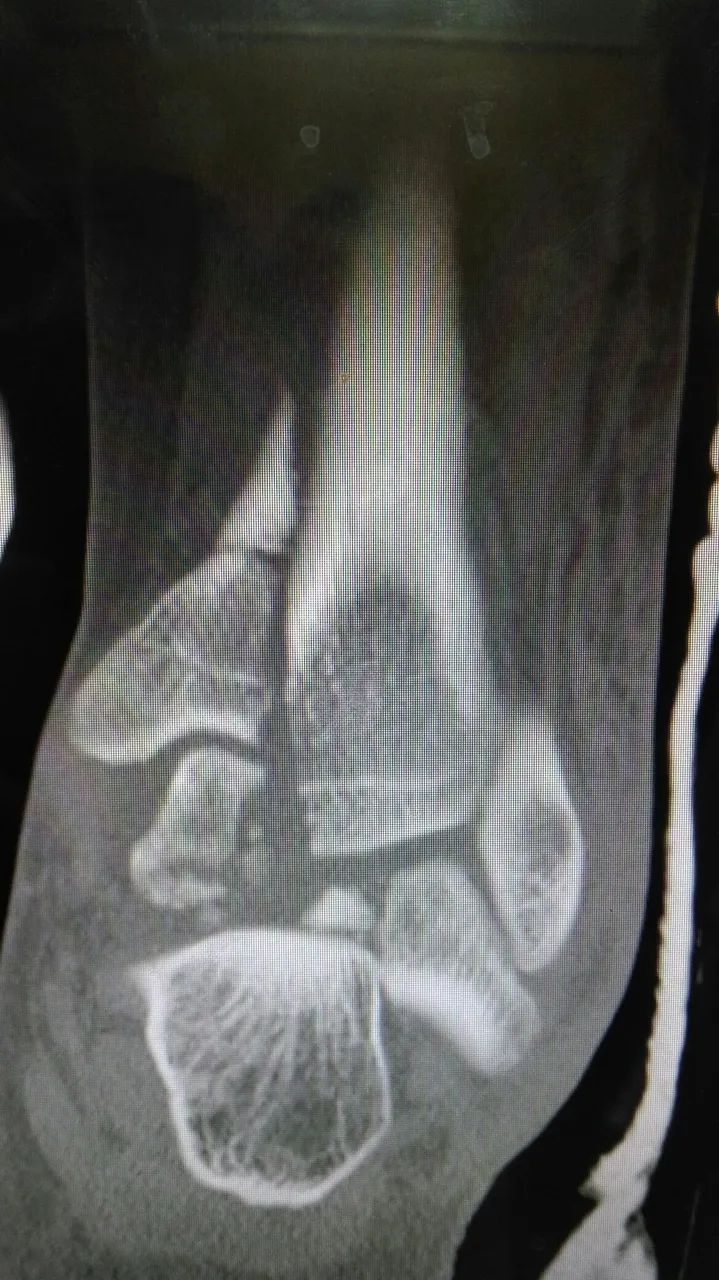

External Fixation

External fixation is a multipurpose treatment method; this is precisely where its versatility lies, and when the orthopaedic surgeon has it at hand and masters its principles and indications, he has the adequate tool to face situations that before its appearance could not be satisfactorily resolved.

This surgical technique has advanced significantly in all continents, becoming the perfect tool to treat temporarily or definitively various pathologies of the locomotor system of congenital aetiology or acquired thanks to its versatile character.

External fixation is a treatment method based on extrafocal handling of bone fragments. As such, its principles for the management of its surgical technique are:

Stability at a distance from the surgical or traumatic lesion. This is achieved by using the criteria of the lever arm that establishes: a) Anchor nails and/or transfictives should be placed at a distance proportional to the longitudinal extension of the fixed segment; for example, if an osteotomy is performed or a fracture is treated at the level of the middle third of the tibia, if the proximal frament measures 13 cm and a fixator with three transfictive nails or three anchor nails (Champ) is to be used, they should be placed at a distance of approximately 4 cm between one and the other.